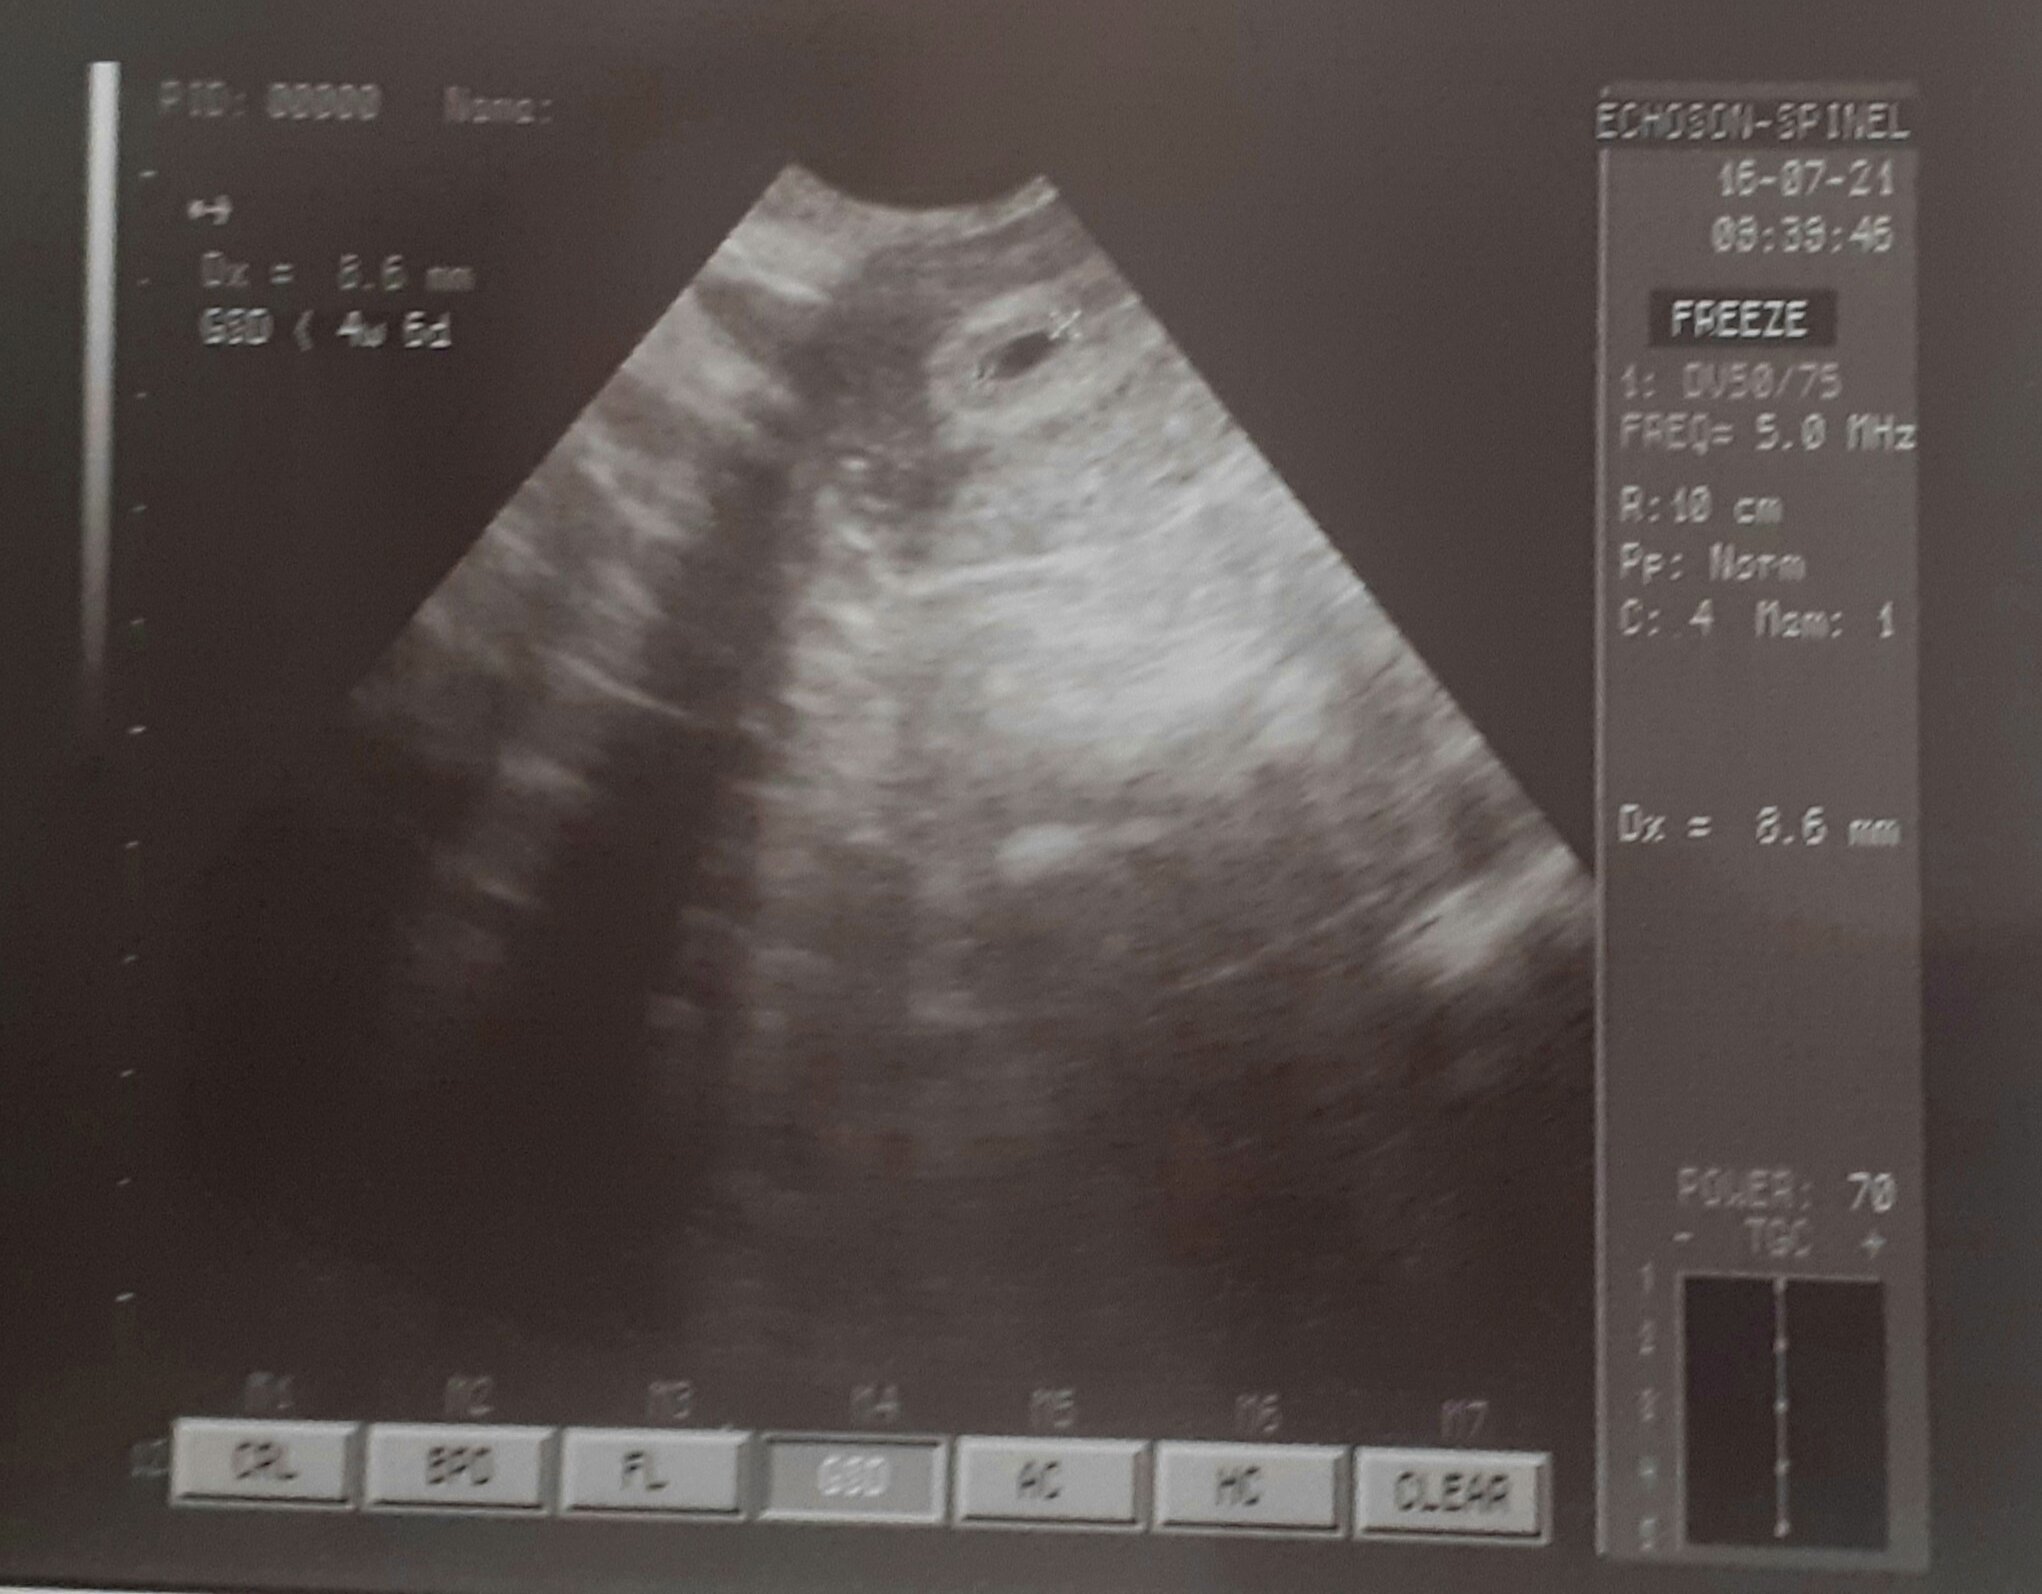

Właśnie wyszłam z pierwszej wizyty i z dumą przedstawiam moj 3mm pęcherzyk 😍 Niestety jest jeszcze torbiel 3x4 ,ale ginekolog uspokajal ,że to czeste we wczesnej ciąży i powinna sie sama wchłonąć .Kolejną wizytę mam dopiero 5.08 i wtedy licze że zobaczę serduszko

Załączniki

• 20210716_110835.jpg